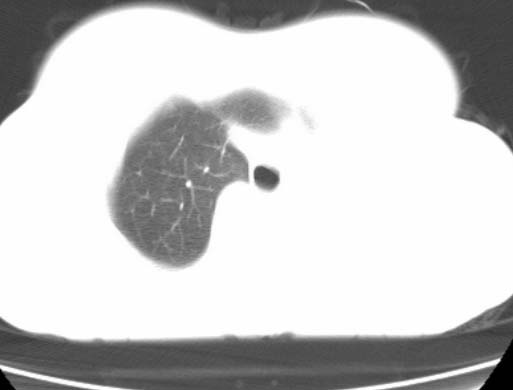

女  20岁。一月前咳血,诊“肺结核”抗痨治疗一月后,咳血停止,现复查。病人精神好。前后ct片对比未见明显变化。既往体检“正常”

1)考虑左肺结核并肺不张、支气管扩张。2)纵隔疝。

考虑左肺结核,左肺毁损,纵膈左偏,既往体检正常不可靠,tb一个月也不会这个样子的,有钙化,应该病程较长,冰冻三尺非一日之寒!

左肺发育不全。

考虑左肺结核,左肺毁损,纵膈左偏,既往体检正常不可靠,tb一个月也不会这个样子的,有钙化,应该病程较长,冰冻三尺非一日之寒

结核,左肺毁损。